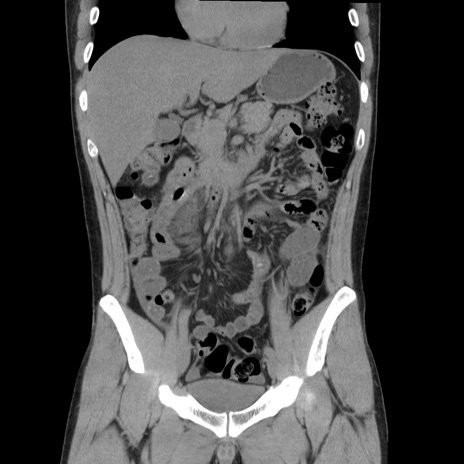

症例36(冠状断像)

【症例】20歳代 男性

【主訴】心窩部痛

【現病歴】今朝より上腹部痛あり。一旦軽快していたが再度出現したため救急要請。昨日夕に白身の魚を含む刺身を食べた。

【身体所見】BP 136/89mmHg、HR 74/min、BT 37.0℃、腹部:膨満、軟、心窩部に圧痛あり。反跳痛なし、筋性防御なし、腸雑音やや亢進あり。

【データ】WBC 17700、CRP 0.48